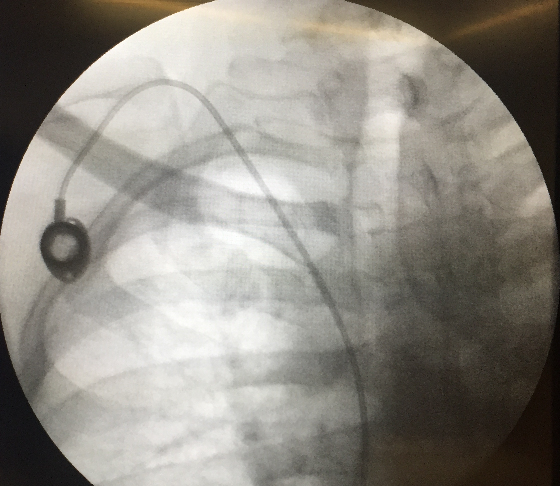

You can't really see the port itself in this picture, I've marked the location

with a red circle, and the two incisions were used by the surgeon

to make it so:

The flouroscope shows it inside:

I really like my port; no getting poked in the arm every time.